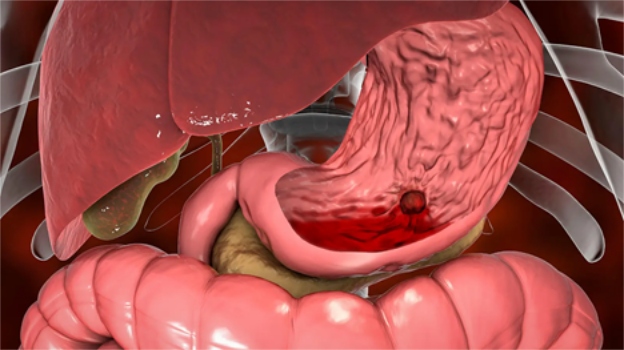

Cảnh báo tình trạng xuất huyết dạ dày nguy hiểm khôn lường

Lão từng gặp không ít bà con, vào đến phòng khám là mặt tái nhợt, môi nhợt nhạt, tay chân lạnh toát… Cứ tưởng thiếu máu thông thường, nhưng bắt mạch, nhìn sắc, hỏi kỹ thì mới vỡ lẽ: đó là hậu quả của xuất huyết dạ dày – căn bệnh âm thầm nhưng nguy hiểm khôn lường nếu không phát hiện và xử lý kịp thời.

Dấu hiệu cảnh báo không được lơ là

Lão nói rõ hơn cho bà con dễ hình dung, xuất huyết dạ dày thường bộc lộ qua một số biểu hiện sau:

- Đau dữ dội vùng thượng vị, đau quặn từng cơn, kèm cảm giác nóng rát.

- Nôn ra máu, máu đỏ tươi hoặc nâu sẫm như bã cà phê.

- Đi ngoài phân đen, mùi hôi khẳm, dính.

- Hoa mắt, chóng mặt, tụt huyết áp – dấu hiệu mất máu cấp.

Bà con nhớ nhé, chỉ cần có 1 trong các dấu hiệu trên, tuyệt đối không nên coi thường. Bởi mất máu dạ dày nếu kéo dài dễ gây tụt huyết áp, sốc, thậm chí nguy hiểm đến tính mạng.